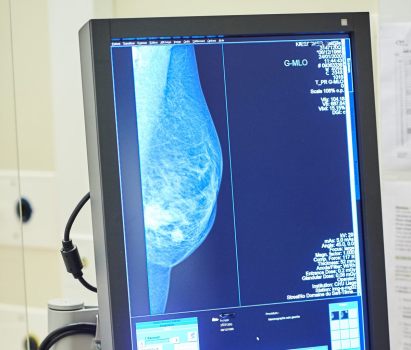

ROMA (ITALPRESS) – A quasi tre mesi dall’istituzione dell’apposito fondo nazionale di 20 milioni di euro, i test genomici per il carcinoma mammario non sono ancora disponibili gratuitamente in tutta Italia. “Per migliorare la qualità di vita delle pazienti e permettere risparmi di preziose risorse pubbliche bisogna accelerare le procedure affinchè questi esami siano disponibili senza alcuna spesa. Per questo chiediamo un intervento diretto e immediato del Ministero della Salute affinchè approvi al più presto il decreto attuativo”. E’ questo l’appello che sostiene Europa Donna Italia, il movimento per la tutela dei diritti delle donne con tumore al seno che a inizio 2021 ha avviato la campagna nazionale “Chemio: Se Posso la Evito”. I principali risultati dell’iniziativa sono stati presentati oggi in una conferenza stampa virtuale. In poco più di due mesi sono state raccolte oltre 15.000 firme ad una petizione on line. Sono poi stati raggiunti oltre 564mila utenti del web attraverso un’intensa attività sui principali social media.

“Questi esami rappresentano una fonte di risparmio importante per i conti pubblici – aggiunge il professore Carlo Tondini, direttore Oncologia Medica dell’Ospedale Papa Giovanni XXIII di Bergamo -. Nello studio BONDX, condotto in Regione Lombardia su 400 pazienti, abbiamo provato a quantificare da un punto di vista economico i vantaggi ottenuti. La ricerca ha evidenziato come l’uso di due test, da 2.000 euro ciascuno, abbia evitato una chemioterapia dal costo di 7.000 euro. Il risparmio diretto sulla spesa farmaceutica regionale ammonta a circa 3.000 euro per paziente a cui vanno aggiunti i costi indiretti per malati e caregiver. Abbiamo, inoltre, evitato ad una donna di essere sottoposta ad una chemioterapia, dopo l’intervento chirurgico, e preservato così la sua qualità di vita evitando effetti collaterali”.